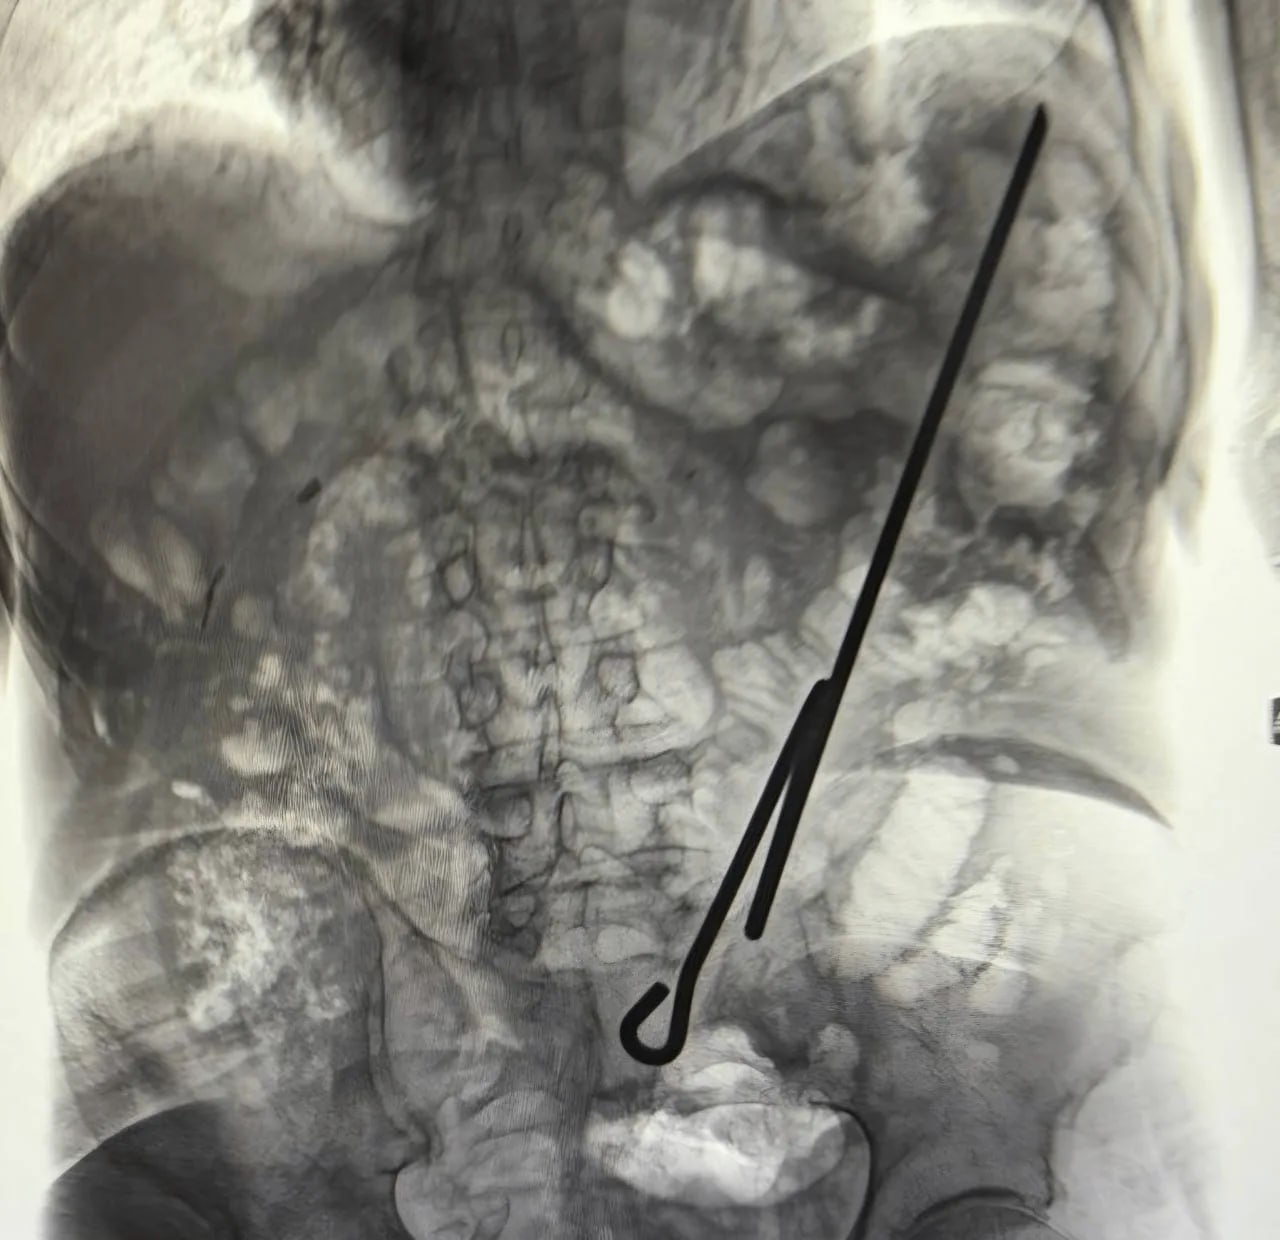

Первый пациент, 84-летний мужчина, получил травму при выполнении домашней работы с помощью самодельного приспособления. В результате падения он напоролся на него, после чего был доставлен в больницу. Хирурги провели срочную операцию, в ходе которой инструмент был успешно удален. Как установили медики, органы брюшной полости не пострадали, чему способствовало и то, что пострадавший был голоден. Послеоперационный период прошел без осложнений, и пациента вскоре выписали.